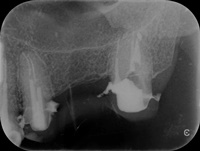

Pacjentka zgłosiła się z bólem. Ząb prawa dolna czwórka po leczeniu kanałowym. Nawracające dolegliwości bólowe, od kilku lat okresowo zaostrzające się. Podjęto decyzję o rewizji leczenia kanałowego. Udróżniono kanał korzeniowy, oraz odnaleziono kanał dodatkowy. Zdjęcie początkowe i zdjęcie po leczeniu endodontycznym pod mikroskopem.